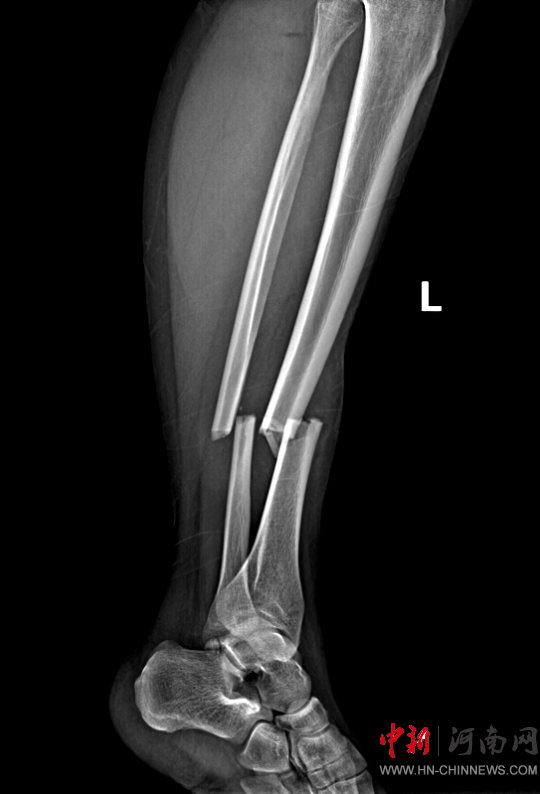

患者,女,32歲,車禍傷,到達確山縣人民醫(yī)院急診科創(chuàng)傷中心救治時血壓80/45mmHg,心率115次/分,處于昏迷、休克狀態(tài),病情危重。急診科迅速啟動創(chuàng)傷中心急救綠色通道,醫(yī)護人員立即展開搶救,積極抗休克治療的同時,聯(lián)系神經(jīng)外科、胸外科、急診重癥監(jiān)護室緊急會診,同時快速CT、床旁FAST檢查明確診斷。通過一系列急救措施,患者的休克狀態(tài)稍微好轉(zhuǎn),經(jīng)多學(xué)科會診后明確診斷為:多處損傷并失血性休克、彌漫性軸索損傷、蛛網(wǎng)膜下腔出血、腦挫傷、股骨及脛腓骨粉碎性骨折、多發(fā)肋骨骨折并肺挫傷、腰椎骨折。ISS評分高達50分,死亡率極高,患者病情危重,立即送入急診重癥監(jiān)護室進行高級生命支持治療。

患者病情好轉(zhuǎn)后,該院急診科主任岳春彥和創(chuàng)傷治療團隊為患者制定了詳細的手術(shù)規(guī)劃,傷后第10日,患者在全身麻醉下進行“左股骨粉碎骨折及脛骨粉碎骨折髓內(nèi)釘內(nèi)固定術(shù)+骨移植術(shù)、腓骨骨折復(fù)位內(nèi)固定術(shù)”,病情平穩(wěn)后轉(zhuǎn)入急診科病房治療,切口愈合后,患者轉(zhuǎn)入康復(fù)醫(yī)學(xué)科進行腦功能康復(fù)和下肢關(guān)節(jié)康復(fù)治療。目前,患者能夠與人正常溝通交流,左下肢關(guān)節(jié)功能也恢復(fù)良好,已出院。